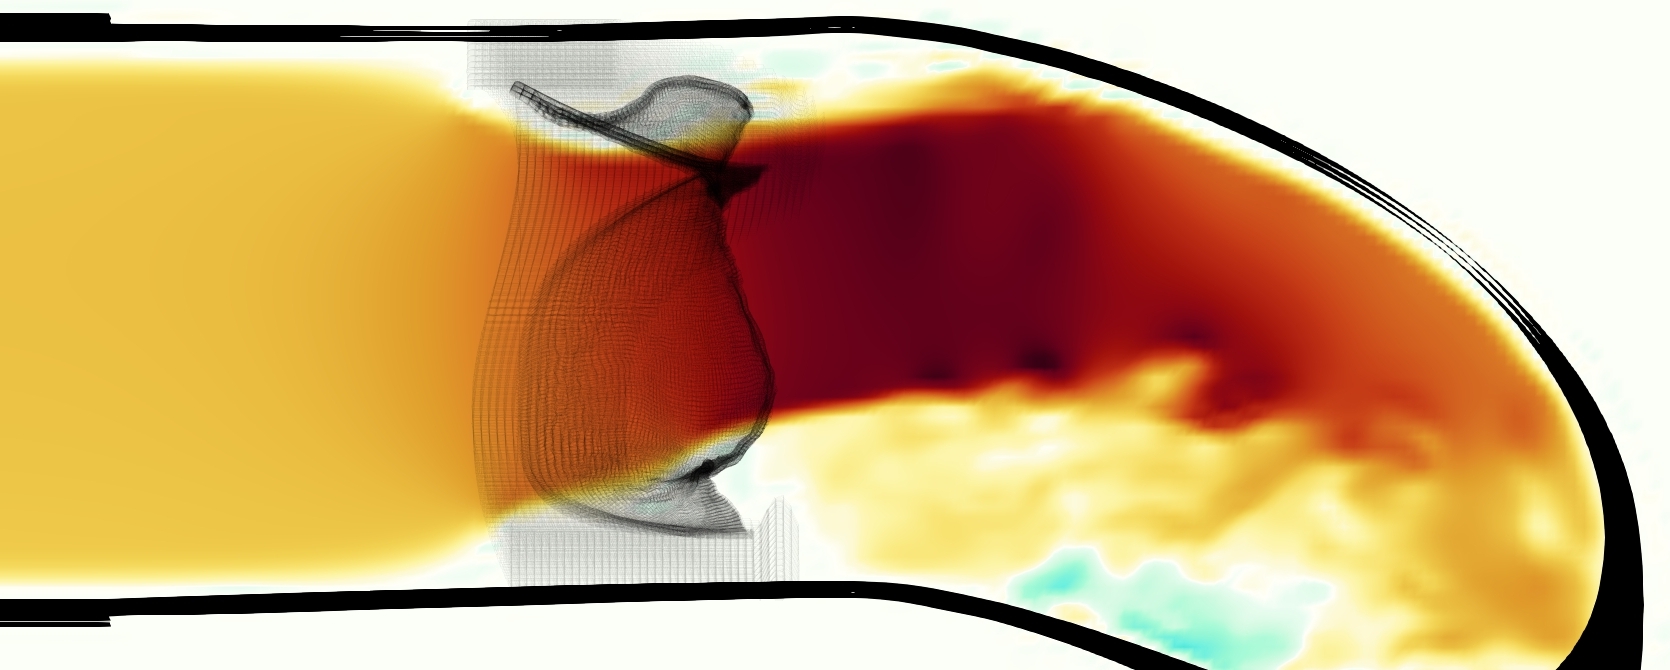

The emergent hemodynamics showed excellent qualitative agreement with experiments. Slice views of the axial component of fluid velocity ( component) in the sagittal plane that cuts through the center of the vessel, parallel to the flow direction, are shown in Figure 5. The flow in both the simulation and the experiment began to accelerate at the same time, with a jet forming through the open valve leaflets. The velocity, angle, and shape of the jet agreed well between the two cases during systole. The simulation captured the slight upward angle of the jet, which was not fully centered in the vessel. It also matched the location where the jet impacts the wall and the slower speed of the jet as it turns with the MPA downstream. As the flow decelerated, the fluid along the interior curve of the vessel reversed first while forward flow persisted where the jet was strongest, as seen in both the simulation and experimental results.

In both the experiment and the simulation, a separation region of reverse flow developed along the interior curve of the vessel under the core jet through the valve. The reverse flow began to develop at the same time in the cardiac cycle and grows throughout systole. The simulation lacked reversed flow in the entire region where reversed flow was present in the experiment, but this region developed some flow separation and had much slower flow than elsewhere in the vessel. Thus, the simulation captured that this is a distinct region from the core jet through the valve opening. There was a smaller amount of slower and slightly reversed flow along the outer curve of the vessel, close to the valve annulus and scaffold support. This region was well-matched between the experiment and the simulation.

A comparison between the phase-averaged velocity resampled onto the MRI grid, the phase-averaged velocity without resampling, the instantaneous flow field without resampling and the MRI velocity field is shown in Figure 8. The coarser resolution is visible as a “stair-stepping” or “pixelated” effect on the phase-averaged resampled velocity, whereas the edges of the jet are more smooth in the phase-averaged velocity with no resampling. Otherwise, the resampled velocity appears qualitatively similar to the phase-averaged velocity with no resampling. Fine scale features were present in the instantaneous field that were lost in the phase-averaging and resampling process. There was more variation in the local velocity of the center of the jet and local areas of high velocity at the edges of the jet that suggested vortices. Vortical structures adjacent to the jet and in the areas of reversed flow were apparent. These comparisons suggest that 4D flow MRI data may lose substantial fine-scale flow features in the flow field via phase-averaging.

The simulated velocity fields showed excellent qualitative agreement with the experimental velocity. Many features of the flow that were present in the experimental measurements also appeared in the simulations, including a large jet which angled up downstream of the valve and the appearance of a triangle-like shape in the jet. A recirculation zone appeared downstream, though the precise region of recirculation showed only some agreement at some points in time. We prescribed the experimentally measured pressures (subject to minor processing as described in Section 3.3), and the emergent flow rates matched those of the experiments.

The simulated velocity fields also showed quantitative agreement with the experimental velocity. The entire flow domain interior to the vessel showed relative error of 30% on velocity magnitude and 36% on the component of velocity during mid-systole. While this certainly leaves room for improvement, we are not aware of any other studies comparing simulated flow around heart valves to experiments that compute relative error on the entire flow field. Similar results were found at and 0.625 cm, and slightly higher relative error downstream at 1.25 cm. The nondimensional streamwise momentum, represented by , was extremely similar in simulation and experiment.

Of potential future interest, the phase-averaged, resampled velocity showed substantial differences from the instantaneous velocity fields, with more variation in local fluid velocity and more fine scale vortical structures visible in the simulation (Figure 8). This points to an advantage for simulations: since 4D flow MRI data is fundamentally phase-averaged, once validated, simulations provide a richer dataset when these instantaneous fluid features are of interest.